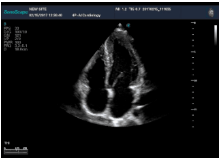

不同的探頭對應(yīng)于不同的臨床領(lǐng)域,不同的探頭頻率也應(yīng)用于不同的人體組織。超聲波在人體中的衰減與探頭頻率有關(guān),探頭頻率越高,穿透力越弱,分辨率越高,而探頭頻率越低,穿透力越強,分辨率越低。因此在檢查淺表器官時應(yīng)選用高頻探頭,而檢查深部臟器時則選用穿透性強的低頻探頭。